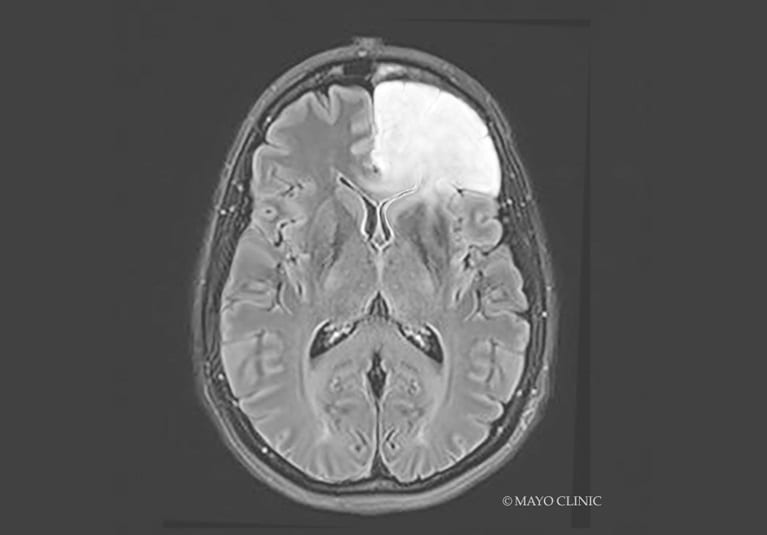

Moyamoya disease: Multidisciplinary care for a complex disorder

Mayo Clinic's approach combines the latest technology with strong clinical experience. Subspecialized experts guide every stage of patient care for this subtle disease.